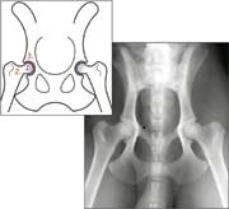

Die gesunde Hüfte:

Die gesunde Hüfte ist ein Gelenkkopf und eine Gelenkpfanne. Das Gelenk muss, für eine

ausreichende Stabilität, genau ineinander passen und sanft rotieren können

1. Der Kopf des Femur (Gelenkkopf) ist groß, rund und glatt

2. Der Hals des Femur ist deutlich ausgeprägt und hat glatte Ränder

3. Die Ränder des Acetabulum (Gelenkpfanne) sind glatt

4. Das Acetabulum ist tief und umschließt mehr als 50% des Femur Kopfes

5. Der Kopf des Femur passt formgenau in die Acetabulum

Auswirkungen der Hüftgelenkdysplasie

Hierbei ist die Gelenkpfanne (Acetabulum) oftmals zu flach und der Gelenkkopf (Kopf des Femur) ist

zu klein und missgebildet. Diese Missbildung kann zur Gelenkinstabilität führen, die eine

schmerzhafte Lahmheit für ein ganzes Leben verursacht.